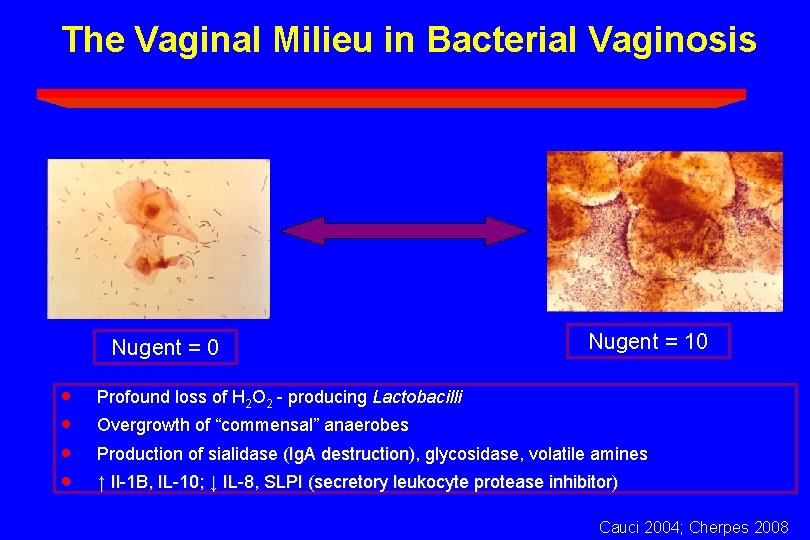

The Vaginal Milieu in Bacterial Vaginosis Nugent = 0 · · Nugent = 10 Profound loss of H 2 O 2 - producing Lactobacilli Overgrowth of “commensal” anaerobes Production of sialidase (Ig. A destruction), destruction) glycosidase, volatile amines ↑ Il-1 B, IL-10; ↓ IL-8, SLPI (secretory leukocyte protease inhibitor) Cauci 2004; Cherpes 2008